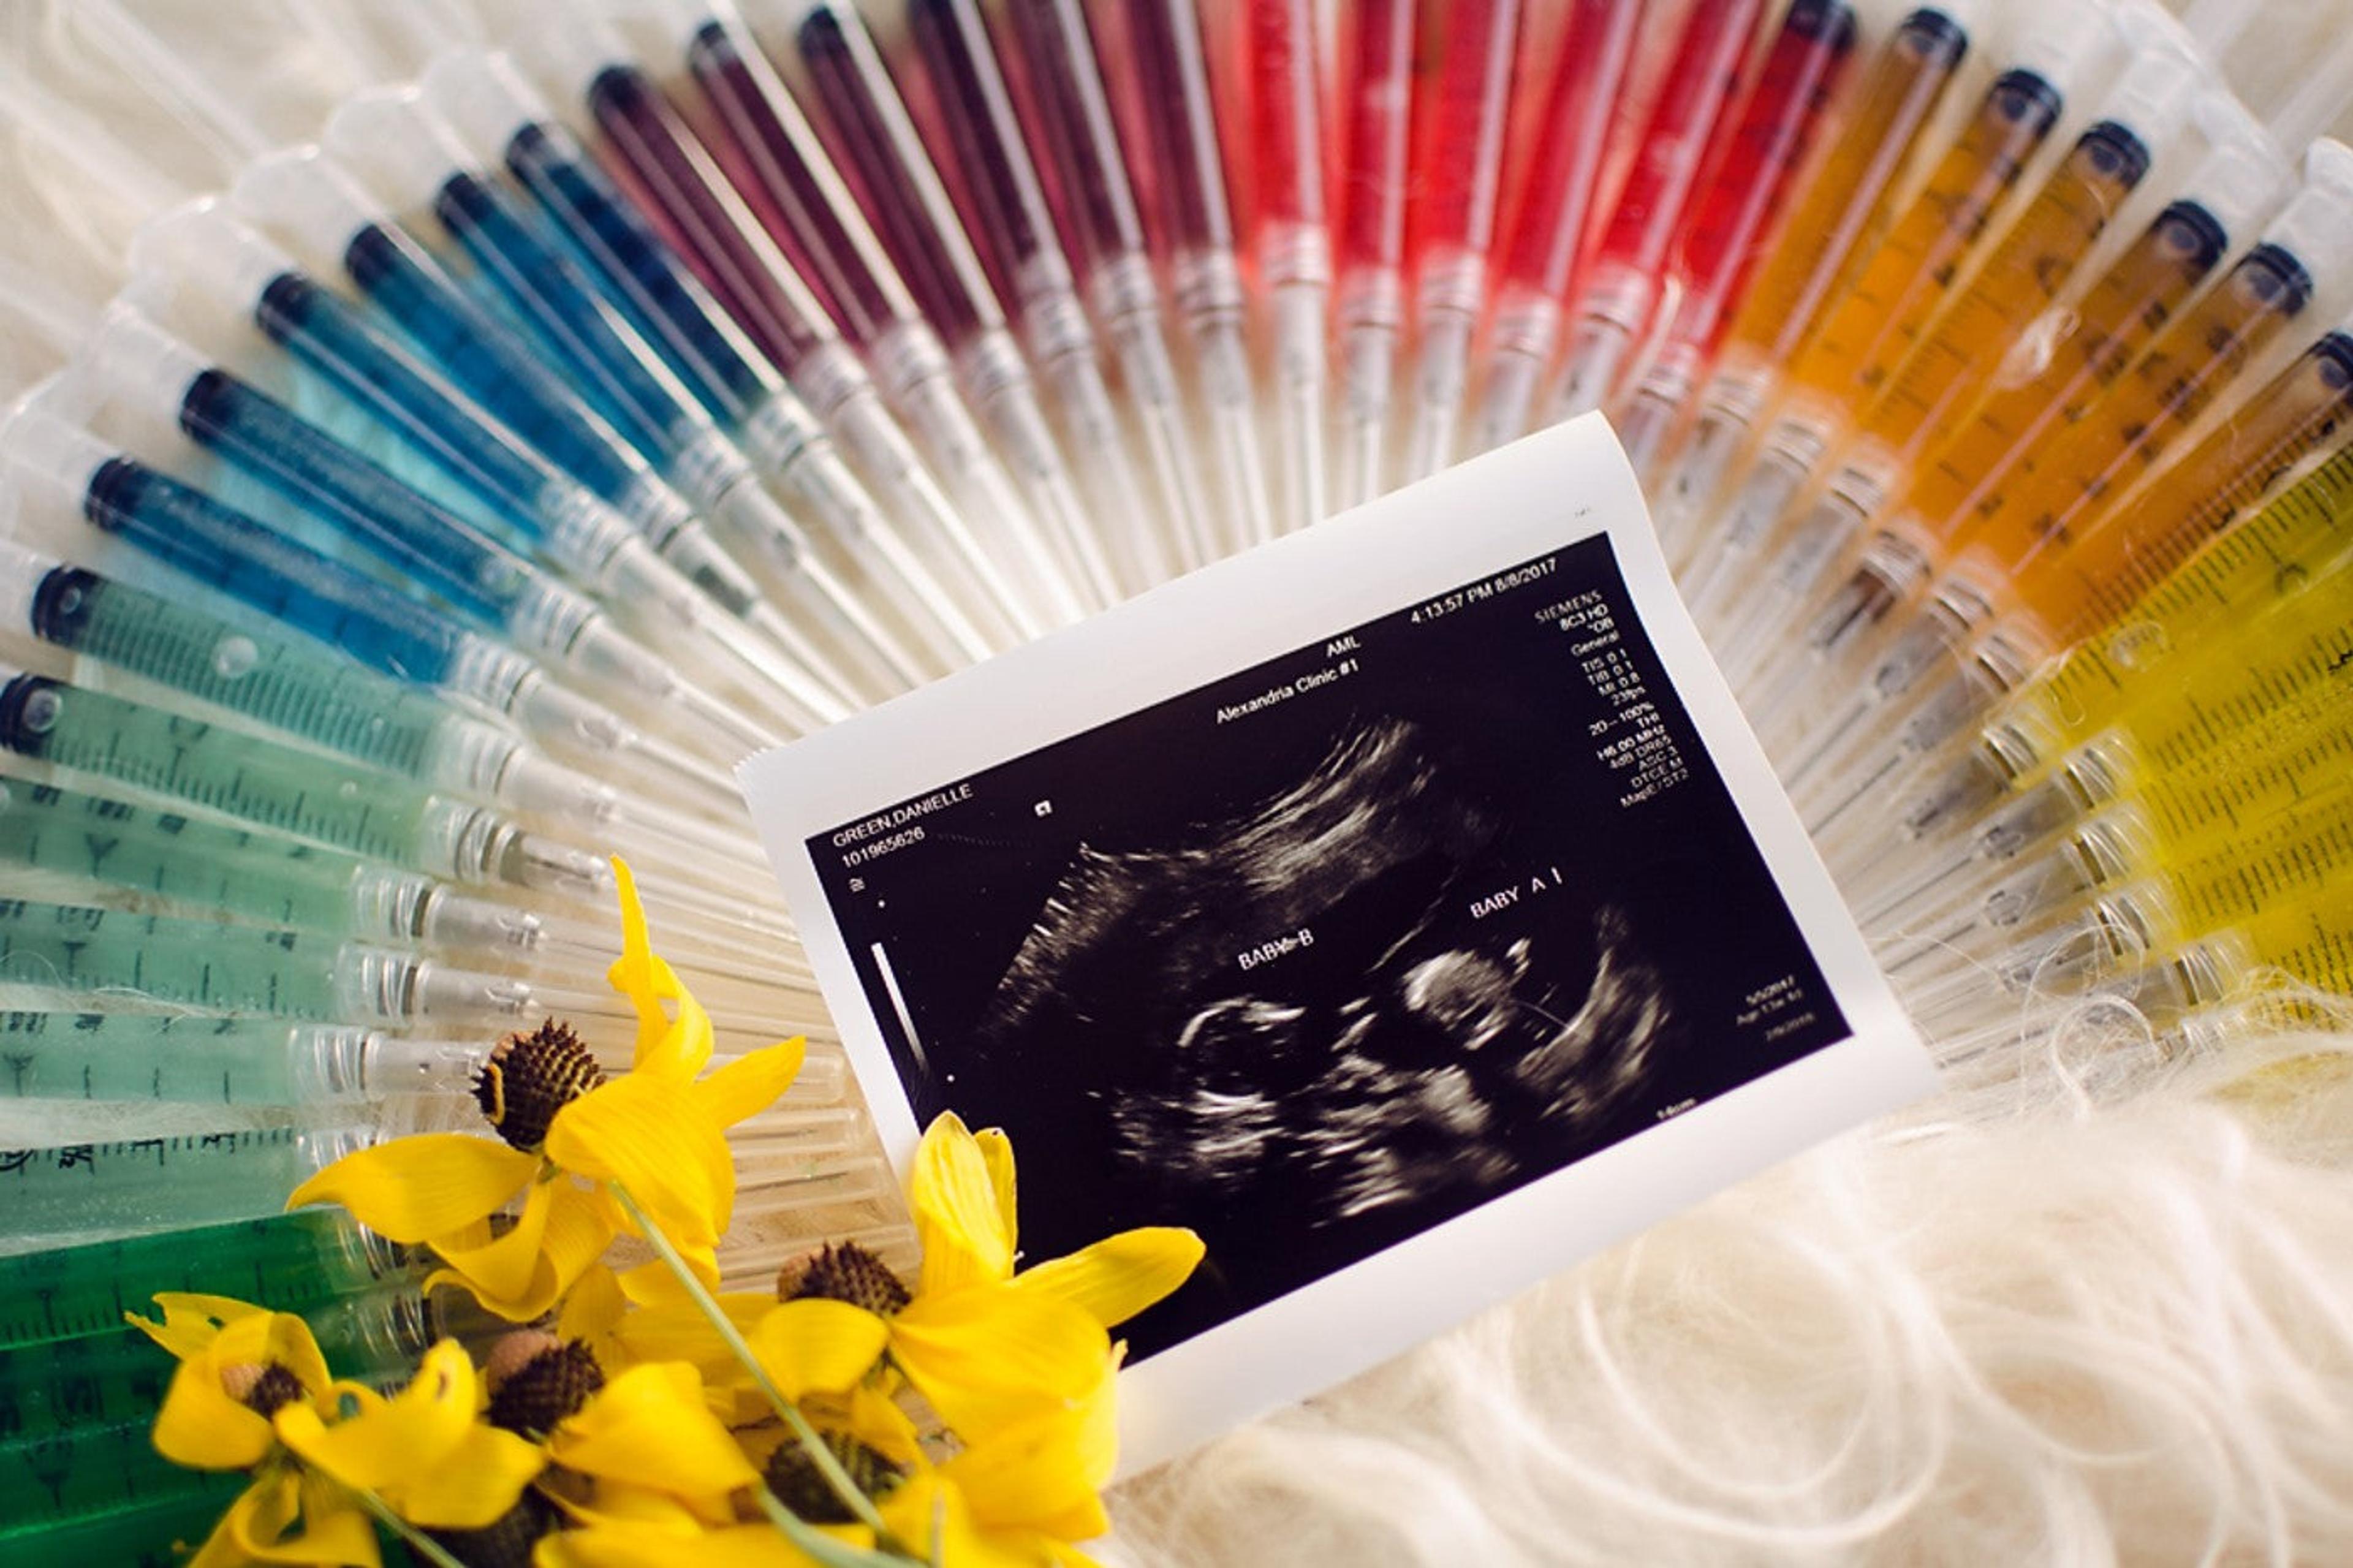

Rainbow IVF Pregnancy Announcement

Photo: The Creative Byte

Another stunning statement with all those saved needles… this is such a gorgeous display for the IVF baby (or babies!) announcement.